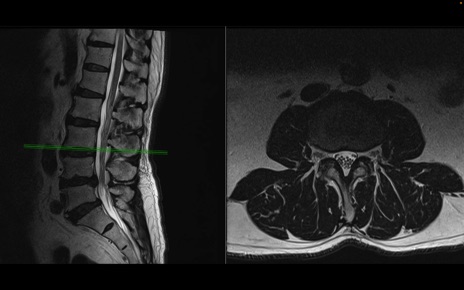

【整形】TIPS症例2 腰椎MRI 横断像と矢状断像

【症例】70歳代男性

【主訴】左下肢痛

【現病歴】2週間前くらいから腰痛、左下肢痛あり。左臀部から大腿、下腿外側のしびれが常時ある。歩行とともに同部位の痛みあり。

【身体所見】Lasegue70-/60+、Bragard-/±、PTR ±/±、ATR -/-、IP 5/5、TA 5/4、TS 5/5、EHL 右第1足趾なし/3、FHL 5/5、hypersthesia(-)、足背動脈触知良好

異常所見と診断は?